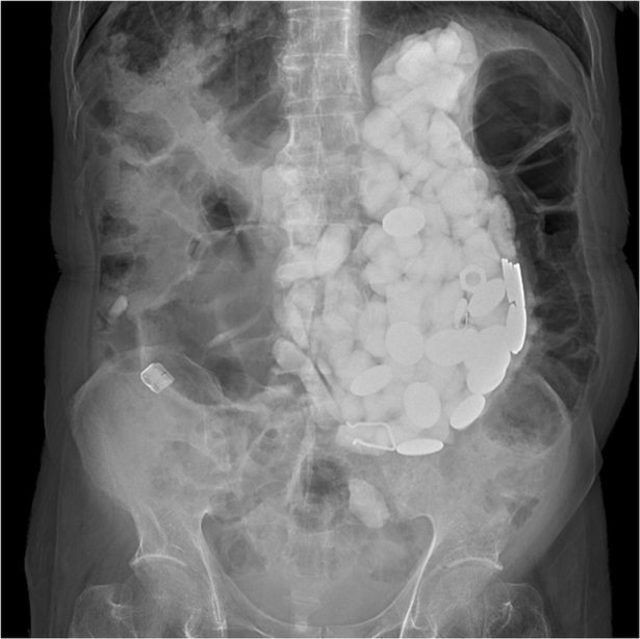

İlginç olay Güney Kore'de gerçekleşti. Adam ağır mide ağrısı ve şişkinlik nedeniyle hastaneye başvurdu. Birkaç tetkikin ardından adamın midesinde yabancı cisimler tespit edildi.

Doktorlar elle yaptıkları muayenelerinde de küçük taşlar hissettiklerini söylediler. Operasyonun ardından adamın midesinden iki kilogram ağırlığında taş, şişe kapağı ve bozuk para çıkarıldı. Tüm olaylardan sonra asıl ilginç olan ise adamın yaptığı açıklama oldu.